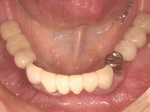

術後、左下奥2本インプラント(鏡像)